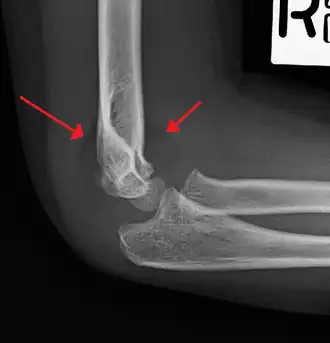

Fat pad sign/sail sign - A non-displaced fracture can be difficult to identify and a fracture line may not be visible on the X-rays. However, the presence of a joint effusion is helpful in identifying a non-displaced fracture. Bleeding from the fracture expands the joint capsule and is visualized on the lateral view as a darker area anteriorly and posteriorly, and is known as the sail sign.[8]

Anterior and posterior sail sign in a child who has a subtle supracondylar fracture -